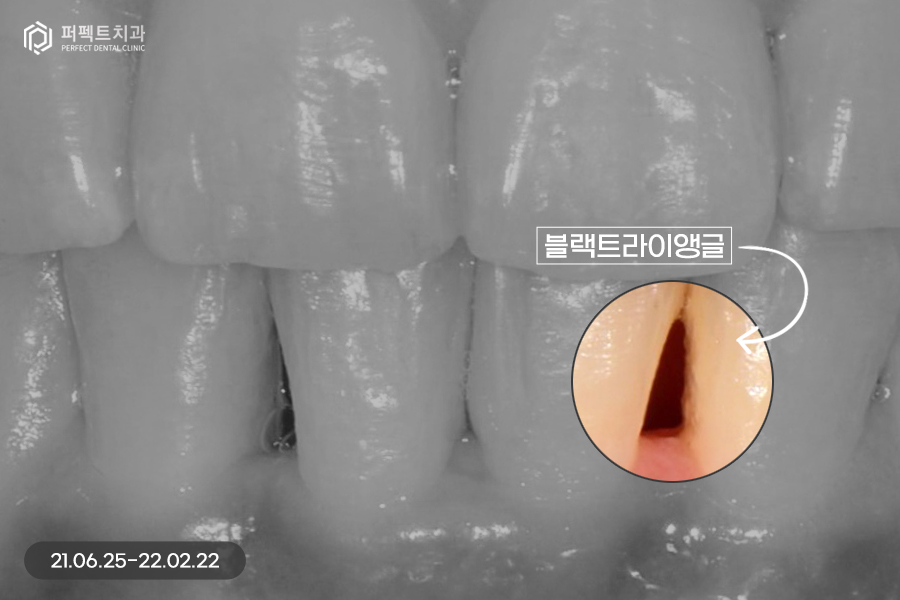

교정 후 치아가 가지런하게 펴졌는데, 교정을 하면 항상 생기는 문제점 중 하나가 바로 고르지 못한 치아들이 가지런하게 펴지면서 잇몸 사이 공간인 블랙트라이앵글입니다.

위 환자분도 마찬가지로 블랙트라이앵글이 발생했고, 이 공간을 해결함과 동시에 치아 색상도 하얗게 변화를 주길 원하셨습니다. 그렇기 때문에 위, 아래 6개 치아를 라미네이트 진행하였습니다.